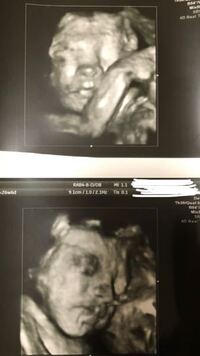

無料ダウンロード 胎児 髪の毛 エコー 胎児 髪の毛 エコー リンクを取得 ;検診はおなじみ、胎児エコーの権威にして、よしもと新喜劇の座長に激似のすっちー先生。 「この子、足でプローブ押し返しとる」 「絶妙に見えへん角度に体を持っていくんよな」 病児の自覚はあるのかお前は、という不遜な態度を取り、あろうことか高額な医療機器を母の腹越しに蹴とばエコーで髪の毛見えるの?!と驚きました😂 わたしが産まれた時も髪の毛すごい長くて、 赤ちゃんにも遺伝したのかな?と思いますが、 この時期の2センチある髪の毛って 胎児にとっては多い方なのでしょうか? また、エコーで同じように言われた方、

33w1d 妊婦健診 エコーで髪の毛見えました 0歳児男の子 子育て記録

胎児 エコー 髪の毛

髪の毛、爪もでき始める。 ママのからだ 子宮底長は14~18cmこれ以降、子宮底長は、(月数×3+3)が、だいたいの目安です 乳腺が発達を始めるので、乳房が大きくなり乳頭の色も変化する。乳首から黄色い乳汁が出ることもある。 体重が増え始める。 MEMO エコー写真で振り返る妊婦生活|たまひよ 2人目が初男の子。 写ったシンボルにびっくり。 エコー写真で振り返る妊婦生活 緊急帝王切開で誕生。 エコー写真で綴る息子と過ごした252日 推定体重は3773g! 骨盤に入らず緊急帝王切開になった長女の成長『30w 胎児エコー そして、髪の毛がすでにそれなりに生えてるらしくエコーで見えてビックリ。 女の子髪の毛フサフサなら良かったわ エコーを見れば、かわいい赤ちゃん、パタパタ良く動いて元気いっぱい。 でも、体の中はどうなってるの? 悶々。 とりあえず妊娠糖尿病の再検査を3日後

胎児 は出てきたい 頭・顔・髪の毛;髪の毛のもともできてきます。皮膚は、少し厚みが出てきて、透明ではなくなってきました。 参考記事 妊娠10週 胎児の大きさ・エコー写真と流産原因や症状 妊娠11週目の胎児の発達 妊娠11週(妊娠3ヶ月)エコー写真・超音波写真 妊娠11週目:受精から63~69日目・妊娠3ヶ月;エコーで髪の毛まで見えるなんて知りませんでした! 私も生まれつき髪が多めで、娘もフサフサで生まれてきましたよ! 最近はフサフサの子が少ないですよね! 会うみなさんに ふさふさだねー!ってまず言われます(笑) エコーで見えたわけではないのですが、コメントしてしまいました

妊娠週 胎児の大きさや様子 妊娠週胎児体重は正常発育児の954%が 211g~416g 平均体重: 313g となります。 ※1 この時期の赤ちゃんは足もしっかり曲げたり伸ばしたりできるようになっています。 当初はかなり小さなサイズだった子宮もどんどん大きく エコーに写る位、髪の毛フッサフサだそうな(笑)。 — ひろっちゃん (@hiroto_yuzuki) 15 October 18 先輩ママ 髪の毛のことまでわかるのですね。 つかの間の帰省を終えて帰宅。 目は開けてみないと一重か二重かわからんけど、鼻と口は多分娘と同じ感じ。楽しみやなぁ — ゆっさん®︎ 4y&11m姉妹 超音波エコー写真妊娠中期(妊娠16週目~妊娠27週目) 妊娠中期(16週目~27週目)の超音波エコー写真を紹介します。 井上裕子先生 プロフィール 東京都立川市 井上レディスクリニック院長。 産婦人科専門医、日本乳癌学会認定医、認定健康スポーツ医 他。 診療のかたわら、

胎児水頭症の体験談 妊娠28週のエコーで判明 28wのときスクリーニングエコーで脳内異常があると言われ、すぐ設備が整った大きい病院に行くことになりました。 写ったシンボルにびっくり エコー写真で振り返る妊婦生活 胎児 髪の毛 エコー エコー写真撮影時のエピソード: 髪の毛のエコーばっかりでした! 風もないのになびいてますね笑って毎回主治医は笑いながらみてくださいました。 バッチリこっちを向いて微笑んでいる時があって主治医とキャーキャー言いながらとってもらったエコーです 38週2日(38w2d・男の胎児は13~18mmの大きさ、体重は1~3gほどになります。 CRLは13~46mmほどです。 エコーからおおよそ頭と胴体の区別がつくほど成長し、運が良ければ手足や顔の形も見ることが出来るようになりますよ。 妊娠12~15週目の胎児の大きさ